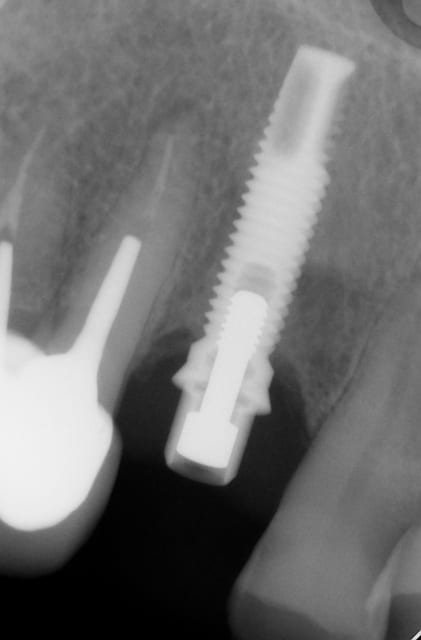

Ci joint une radio d'un implant posé il y a une quinzaine d'année, qqun pour m'aider à l'identifier ? Pluton ?

3i??? fullosteit parallel

Nobel mk3

la différence se situe au niveau apical...c'est subtil mais sur le biomet il n'y a pas cette épaisseur de titane dans la zone des angles de coupe à l'extrémité apicale

La connexion est hex externe ? De toutes façon c'est pareil, biomet ou nobel.

hexagone externe merci à tous